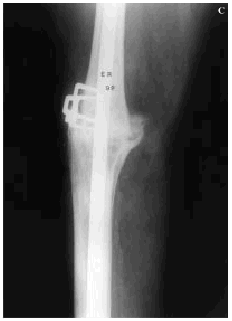

En nueve pacientes, el fracaso de la artroplastia se debió a la infección profunda (Fig. 2), aislando gérmenes del género Staphylococcus en siete de ellos. De los nueve pacientes restantes, en ocho el fracaso de la artroplastia fue debido a un aflojamiento aséptico (Fig. 3) y el caso restante fue causado por una artrofibrosis.

Figura 2. Fracaso séptico artroplastia de rodilla en mujer de 75 años. A: Radiografía preoperatoria. B: Control postoperatorio artrodesis de rodilla con clavo intramedular.